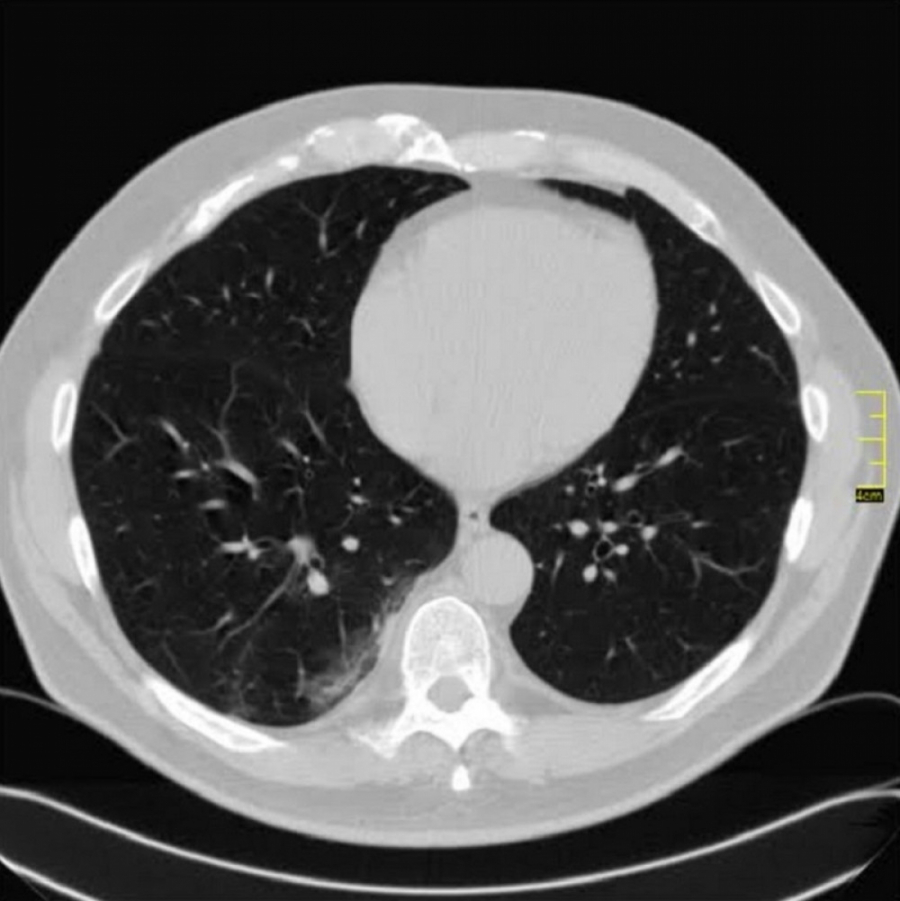

"Zadnjih deset dana se menja radiološki nalaz. Ne kod svih pacijenata, već kod jednog dela. Ali da krenemo redom.

Krenulo je sa divljim sojem. Znamo da je i on imao svoje varijante. Ono što je bilo u samom početku kod nas je ličilo na samu osnovu.

Kada se pogleda pažljivo i deluje divlje, nema neke pravilnosti.

Neki međusoj je bio u leto 2020. Decembar i januar je dominirao britanski soj. Kada se pogledaju njegove slike vidi se razlika u odnosu na divlji, a blizu je onoga koji je bio u leto 2020. godine.

Decembar, januar, februar, mart. 2020/21.

Gustina promena je različita, razlikovala se i klinička slika. retko u decembru ali do marta skoro isključiv.

April 2021. Počinju da dolaze pacijenti koji imaju drugačiji nalaz.

Ono što je karakteristično je to da su ovo nalazi koji su 2. i 3. dana bolesti u I fazi.

Znači ne u progresivnoj, već u uvodnoj fazi kada uglavnom nema CT znaka. Fibrozne trake već drugog dana? Ground glass oko većih grana bronha. Kao da bolest ne može da sačeka, kao da klija gde stigne.

Klinička slika se razlikuje od britanskog soja. To se slažu i moji pulmolozi. Za sada je desetak pacijenata (kod mene), malo za zaključke, ali to su pacijenti u kratkom vremenskom periodu od 31.03.2021. godine do 14.04.2021. godine.